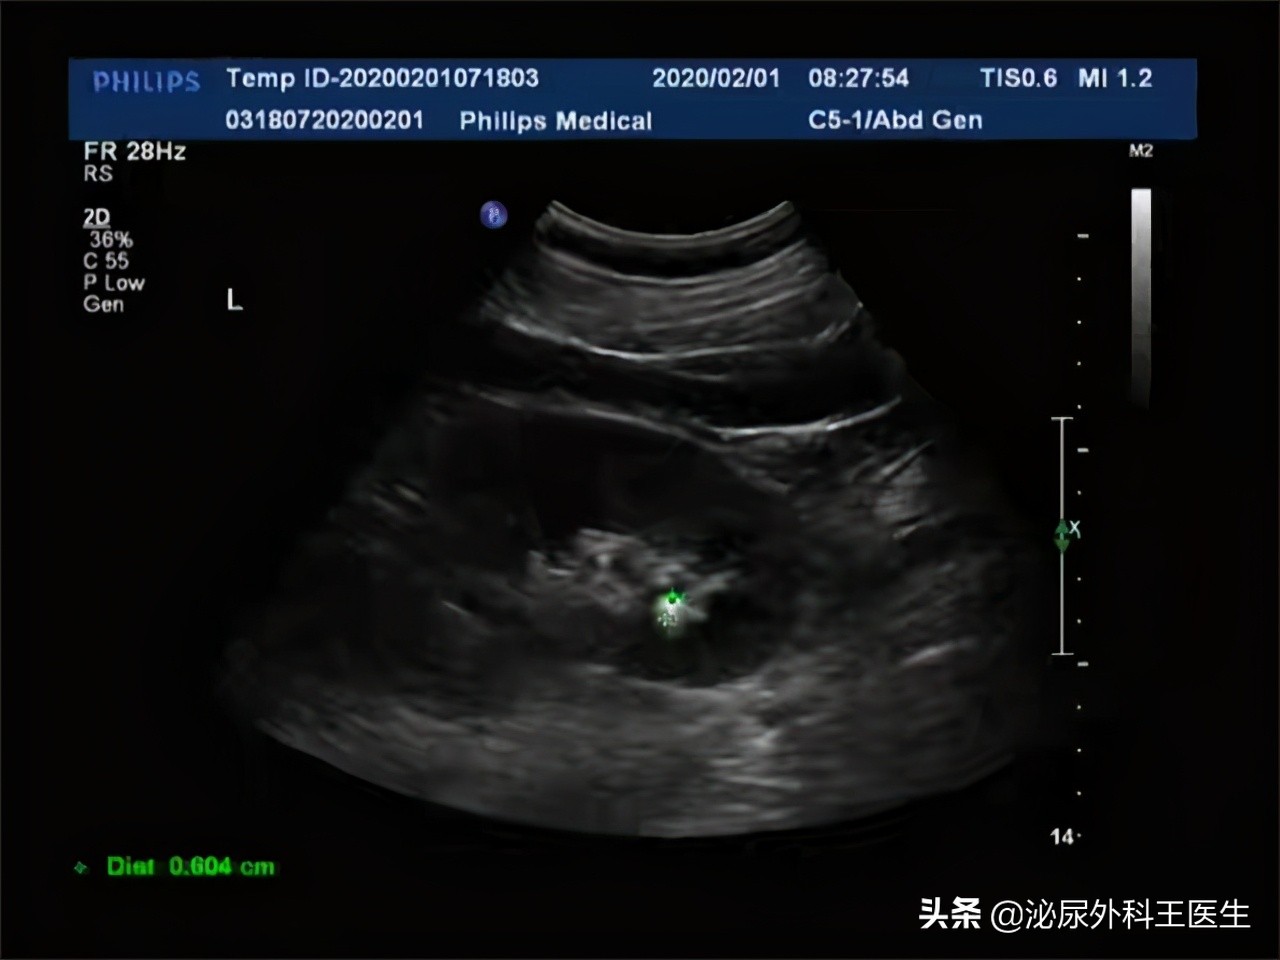

服用排石颗粒来治疗泌尿系结石虽然有用,但这是属于一种比较保守的治疗手段,对于 小于0.6厘米 的结石服用结石颗粒可以对输尿管进行局部的扩张,从而起到促进软化排出的作用,但是如果尿道内的结石大于0.6厘米,排石颗粒这种方法可能会过于温和,疗效不明显,需要辅助医生的碎石的方法。

1.比较小的结石 。排石颗粒可以排出直径小于0.6厘米的结石,而对于大于0.6厘米的结石需要通过手术的措施取出。